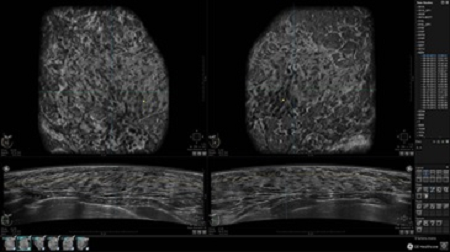

GE INVENIA ABUS – это современный УЗИ аппарат, который создан для точной и эффективной диагностики сканирования с высокой плотностью молочных желез. Выявляемость патологий раковых и предраковых стадий заболевания составляет 55%, что в конечном счете позволяет ставить врачу точные и своевременные диагнозы. Традиционные методы использования маммографии не показывают такой выявляемости, ограничиваясь лишь 3-38%.

УЗИ-аппарат GE INVENIA ABUS позволяет проводить максимально операторонезависимые процедуры, что значительно снижает риск неправильной постановки диагноза и сопутствующие издержки на обработку информации. Система готовит отчет в течение 3-х минут после сканирования, это безусловное преимущество по сравнению с обычным УЗИ сканером.

• Одновременный просмотр двух изображений для сопоставления в коронарной плоскости

• Стандартизованная ориентация изображения: «толстый срез» в коронарной плоскости; поперечная; сагиттальная плоскость; радиальный и антирадиальный поворот изображения; просмотр исключительно области интереса